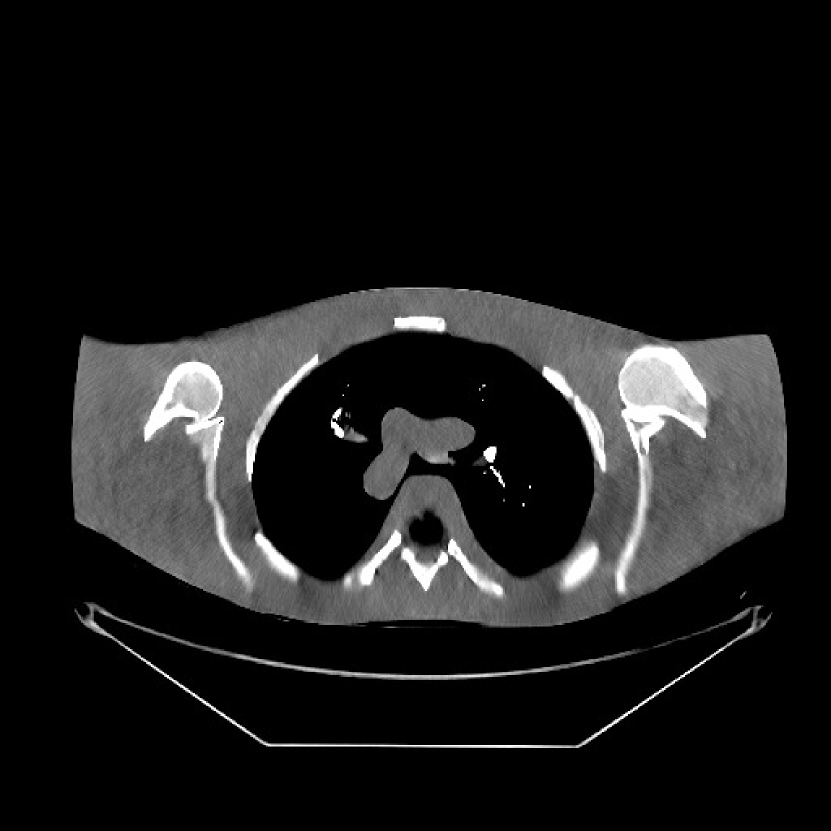

Refer to caption

Figure 1: Reconstruction targeted ROI of the true XCAT phantom displayed with central slices along the axial, sagittal and coronal directions. The display window is [800, 1200] HU.

We simulated 3D axial cone-beam scans using a 840×840×9684084096840\times 840\times 96 XCAT phantom with Δx=Δy=0.4883subscriptΔ𝑥subscriptΔ𝑦0.4883\Delta_{x}=\Delta_{y}=0.4883 mm and Δz=0.625subscriptΔ𝑧0.625\Delta_{z}=0.625 mm. We generated sinograms of size 888×64×98488864984888\times 64\times 984 using GE LightSpeed cone-beam geometry corresponding to a mono-energetic source with I0=1×104subscript𝐼01superscript104I_{0}={\color[rgb]{0,0,0}1\times}10^{4}, 5×1035superscript1035\times 10^{3}, 3×1033superscript1033\times 10^{3}, and 2×1032superscript103{2\times 10^{3}} incident photons per ray and no scatter, respectively. Tab. I shows percentages of non-positive measurements under different dose levels. We set these non-positive measurements to 1×1051superscript1051\times 10^{-5} for generating the post-log sinogram that PWLS-based methods rely on [13]. We reconstructed the 3D volume with a size of 420×420×9642042096420\times 420\times 96 at a coarser resolution of Δx=Δy=0.9766subscriptΔ𝑥subscriptΔ𝑦0.9766\Delta_{x}=\Delta_{y}=0.9766 mm and Δz=0.625subscriptΔ𝑧0.625\Delta_{z}=0.625 mm. The patch size during reconstruction was 8×8×88888\times 8\times 8 and the stride was 3×3×33333\times 3\times 3. For evaluating reconstruction performance, we chose an ROI that was composed of the central 64 out of 96 axial slices, and refer to it as the reconstruction targeted ROI. Fig. 1 shows the central slices of the true XCAT phantom inside this ROI along three directions. In the reconstruction stage of PWLS-ULTRA and SPULTRA, we used 4 iterations for the image update step, i.e., P=4𝑃4P=4, for a good trade-off between algorithms’ convergence and computational costs. We used 121212 ordered subsets, i.e., M=12𝑀12M=12, to speed up the algorithm. The initial image for the ULTRA methods was reconstructed by PWLS-EP, whose regularization parameter was set empirically to ensure good reconstruction quality as βep=213subscript𝛽𝑒𝑝superscript213\beta_{ep}=2^{13} for all the experimented dose cases. We used an analytical filtered back-projection (FBP) method FDK [59] to initialize PWLS-EP. The FDK images of XCAT phantom for all the dose levels are shown in the supplement. Due to the fact that SPULTRA has a similar cost function as PWLS-ULTRA in each outer iteration, we used the same parameter settings for both methods: β=4×104𝛽4superscript104\beta=4\times 10^{4} and γc=4×104subscript𝛾𝑐4superscript104\gamma_{c}=4\times 10^{-4}, which we observed worked well for all the dose levels we tested.